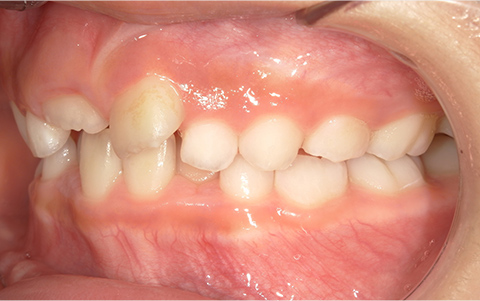

症例